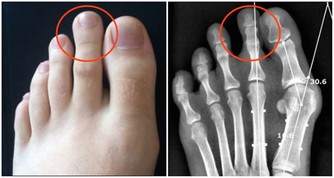

肝臟在人體起著藏血的作用,當肝臟出現異常之後就會使手掌的大小魚際出現了充血的現象,顏色會變得像硃砂一樣的紅色,用手加壓之後就會變成蒼白色,然後又慢慢恢復成紅色,這種情況被稱作“肝掌”,是肝臟腫大的標誌,患者的病情越嚴重,手掌就會變得更紅。